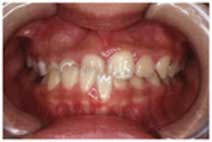

26. 偏位を伴った交叉咬合

左右非対称な形で交叉咬合がある人の場合、顎や歯ならびが曲がってしまう事があります。(歯ならびの真ん中や顎が、左右にずれていることを矯正治療では偏位と言います)

このように、左右非対称な交叉咬合は、放置しておくと、骨が変形してしまうことがあります。